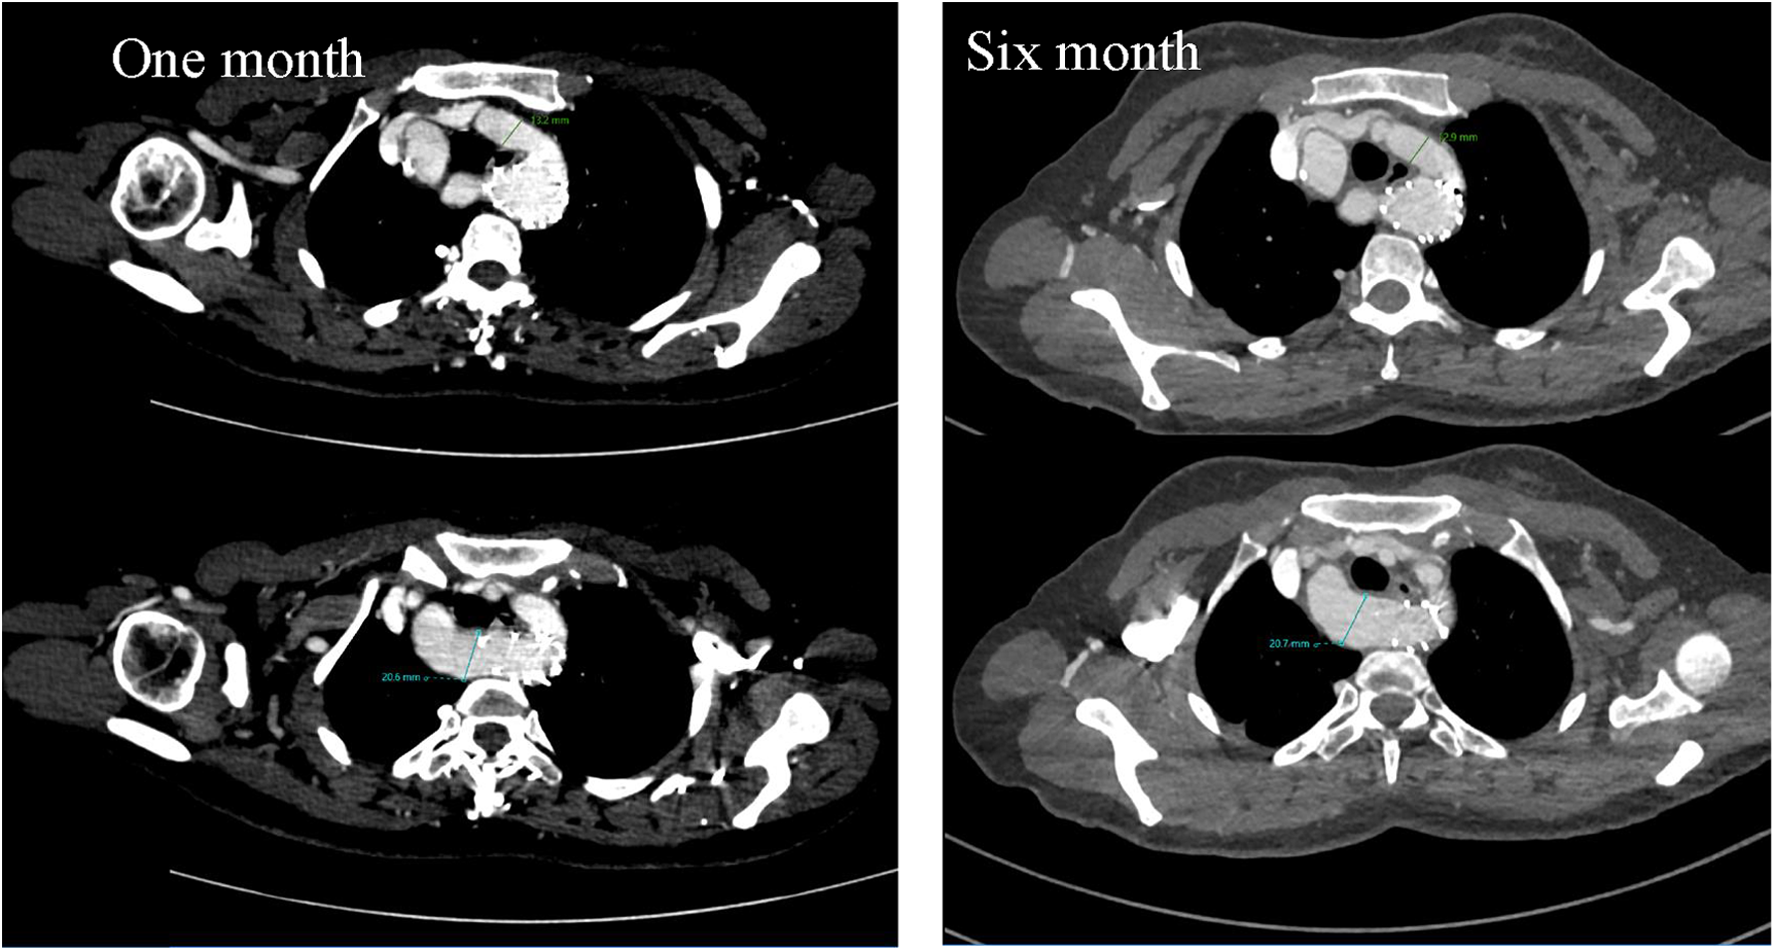

A TEVAR procedure was performed. Considering that the deformity did not cause any clinical symptoms and that the vessel diameter and distance from the proximal anchoring area were sufficient, we decided to anchor the proximal bare stent area to the posterior portion of the dominant arch, and at the meantime, the bare region would not obstruct the non-dominant arch flow, preserving the original aortic arch blood flow (Figure 4). Follow-up CTA scans at one- and six-month post-operation showed that the aortic stent was well-positioned, with no visible primary lesion. The patient reported complete resolution of chest pain and no difficulties with swallowing or breathing (Figures 5, 6).

Figure 5. Cross-sectional images of postoperative CTA at one month and six months suggested no significant changes in dominant and non-dominant arch diameters and no obvious change as preoperatively.

Figure 6. Three-dimensional reconstruction images of postoperative CTA at one month and six months suggested good stent positioning, with no visible evidence of the primary lesion.

The decision-making for treatment strategies could be complicated when congenital and acquired diseases occur in close structural proximity, and the challenge for DAA combined with type B aortic dissection was the abnormal arch malformation. Surgical treatment of related cases is rarely reported in the literature. Midulla (9) and Min (10) performed thoracotomy on three patients with DAA complicated by type B aortic dissection, transecting the non-dominant arch to relieve tracheal and esophageal compression from the vascular ring and performing graft replacement. However, intraoperative complexities included prolonged dissection and reconstruction times. With advancements in endovascular devices and techniques, TEVAR has become highly customizable and minimally invasive is now widely applied in the treatment of various complex type B aortic dissections (11, 12). In patients with DAA combined with type B aortic dissection, when there is no clinical or imaging evidence of significant tracheal or esophageal compression, preserving and reconstructing the original vascular ring structure while addressing only the dissection may offer a simplified yet effective approach. Zhao et al. (13) performed a TEVAR procedure on a patient with DAA and type B aortic dissection, reconstructing the right common carotid artery, left common carotid artery, dominant arch, and non-dominant arch. As we thought that the characteristic “Oversize” feature of the stent might exacerbate vascular ring compression. Consequently, the posterior section of the dominant arch was chosen as the proximal anchorage zone, and a stent with proximal bare zone was deployed to maintain blood flow to the distal non-dominant arch and preserve the integrity of the vascular ring. Follow-up CTA results at one and six months postoperatively demonstrated complete exclusion of the aortic dissection without significant changes to the vascular ring structure.